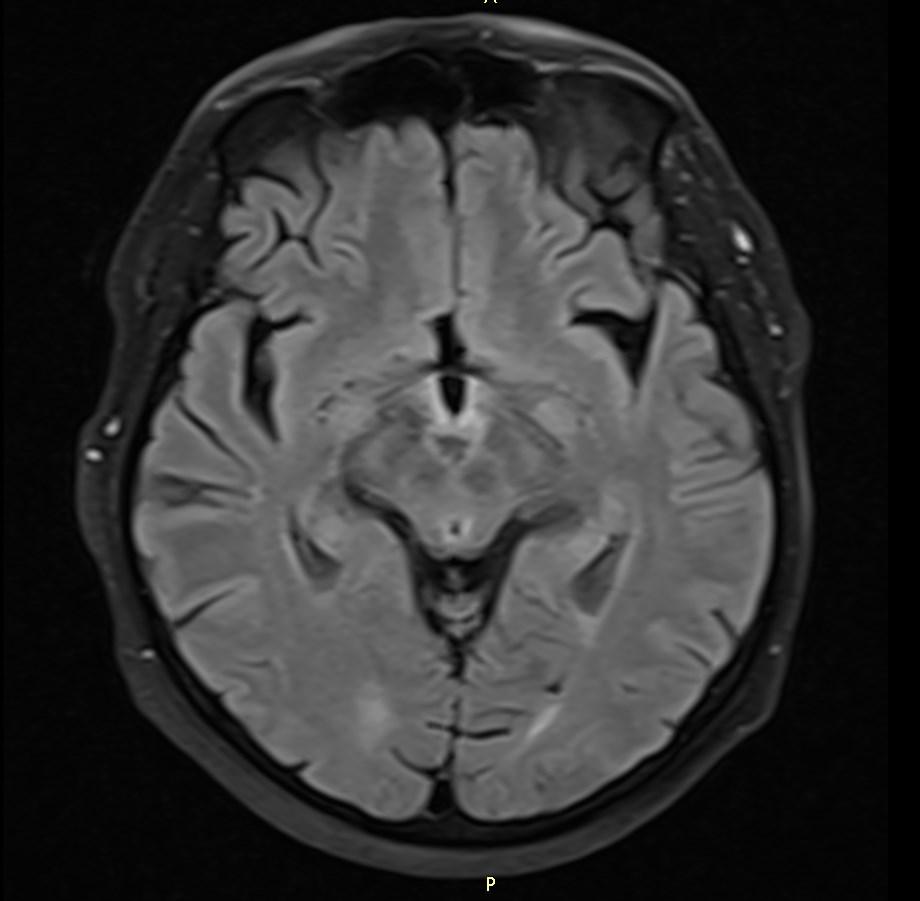

MRI images revealed hyperintensities in the periaqueductal region and the medial thalami.

T2/FLAIR: symmetrically increased signal intensity in the mamillary bodies, dorsomedial thalami, tectal plate, periaqueductal area, and around the third ventricle.